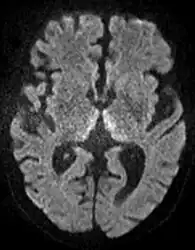

Axial MRI FLAIR image showing hyperintense signal in the periaqueductal gray matter and tectum of the dorsal midbrain.